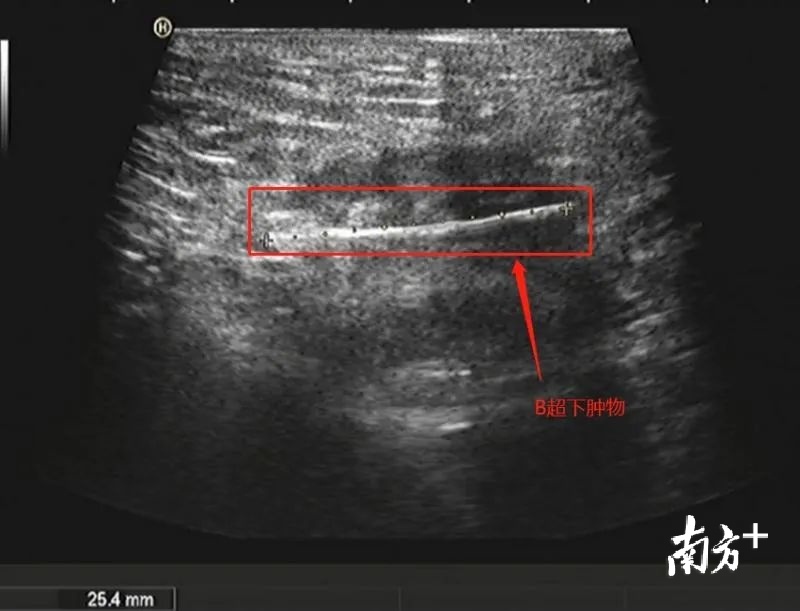

尹医生考虑异物已深入部分肛门内括约肌,而且在不清楚异物的大小及长度的情况下,在门诊直接取出易引起异物断裂、残留,或异物取出后出现肛管出血,止血困难等情况,建议李小姐办理住院在麻醉下手术取出。李小姐住院以后,尹医生马上安排了直肠肛管彩超及盆底CT以进一步明确异物的位置及大小。

根据盆底CT回报考虑异物已穿破直肠壁层。手术中在没有看见异物的情况下,医生凭借B超及CT检查,判定异物垂直插入直肠下段,并穿破直肠壁,进入粘膜下层的位置,最后在切开部分直肠下段粘膜,在距离肛管2厘米处,找到了一米白色异物尾端,并取出。